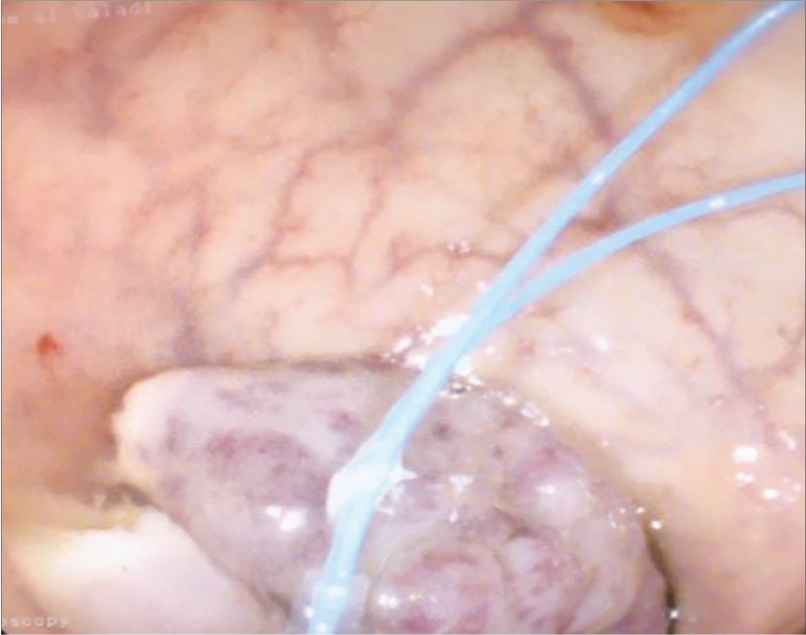

Endoloop snare polypectomy performed on the pedunculated polyp

A 33-year-old male Yemeni national who resides in Riyadh, Saudi Arabia (and often visits Yemen) was referred to the gastroenterology department by a surgical team with a rectal pedunculated polyp and a history of polyp prolapse via the anus during defecation. The polyp was associated with constipation and rectal bleeding. However, the patient did not complain of any upper gastrointestinal symptoms, abdominal pain, weight loss, fever, or symptoms of anemia. A Complete Blood Count (CBC) as well as prothrombin time and international normalized ratio were done. Then the patient refused to have additional laboratory tests. His CBC showed a low neutrophil and absolute neutrophil count (1.87 × 109/L; normal range, 2.0–6.9 × 109/L), and a high monocyte (0.68 × 109/L; normal range, 0.2–0.7 × 109/L) and eosinophil percentage (7.7%; normal range, 1–6%). The rest of his laboratory results were normal. A colonoscopy was performed, and it showed a large (2 × 2.5 cm2) mobile polyp with a large stalk in the rectum (Figures 1 and 2). It was about 8 cm from the anal verge. An endoloop snare polypectomy and a biopsy were performed, resulting in the unusual findings of several schistosome eggs along with inflammatory reaction, which prompted us to give the diagnosis of retention polyp with extensive colonic schistosomiasis (Figure 3).